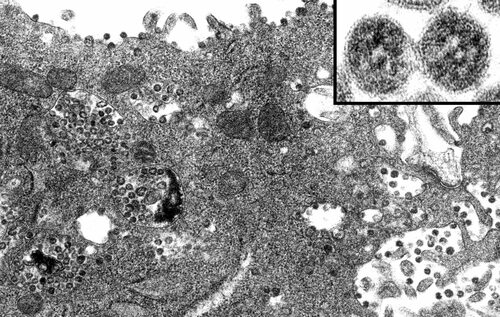

Микрофотография клетки печени позволяет нам увидеть внутреннюю структуру клетки в деталях и лучше понять ее функциональность. Клетка печени имеет характерную форму и уникальные особенности, которые можно увидеть на микрофотографии.

На микрофотографии видно ядро клетки, окруженное митохондриями и другими клеточными компонентами. Также можно увидеть сеть эндоплазматического ретикулума и аппарат Гольджи, которые выглядят как сложные системы мембран и внутренних структур.

Микрофотография клетки печени животного позволяет нам взглянуть на удивительный мир микромасштабных структур, которые образуют основу жизни организма. Они напоминают нам о сложности и красоте клеточной структуры, которая лежит в основе всех живых существ.